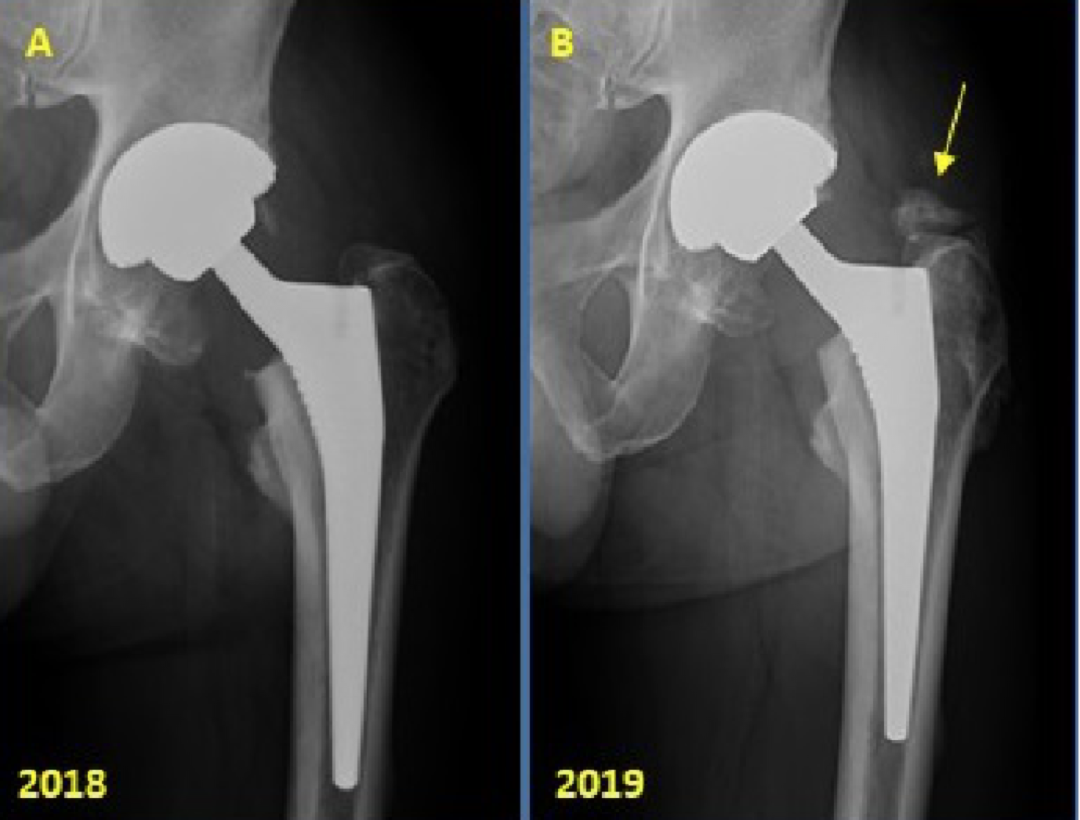

5. Metal-on-metal(MOM)disease:

假性滑囊,是金属对金属髋关节置换的组织反应;表现为髋关节假体周围的滑囊。最常见的部位是:髋臼上缘、大粗隆和小粗隆。

人工髋关节置换术。假体周围囊性肿块(箭头)